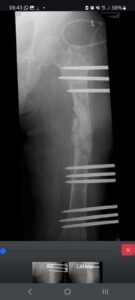

Ia telah menjalani berulang kali operasi, mulai dari pemasangan pen hingga pencangkokan tulang. Infeksi yang tak kunjung sembuh membuat tulangnya keropos dan rusak. Selama dua tahun, kakinya terus mengeluarkan cairan infeksi, nyeri hebat, dan harus dirawat hampir setiap hari.

Kini, Pak Supriyadi kembali dirujuk ke RS Ortopedi Prof. Dr. R. Soeharso Surakarta, Solo.